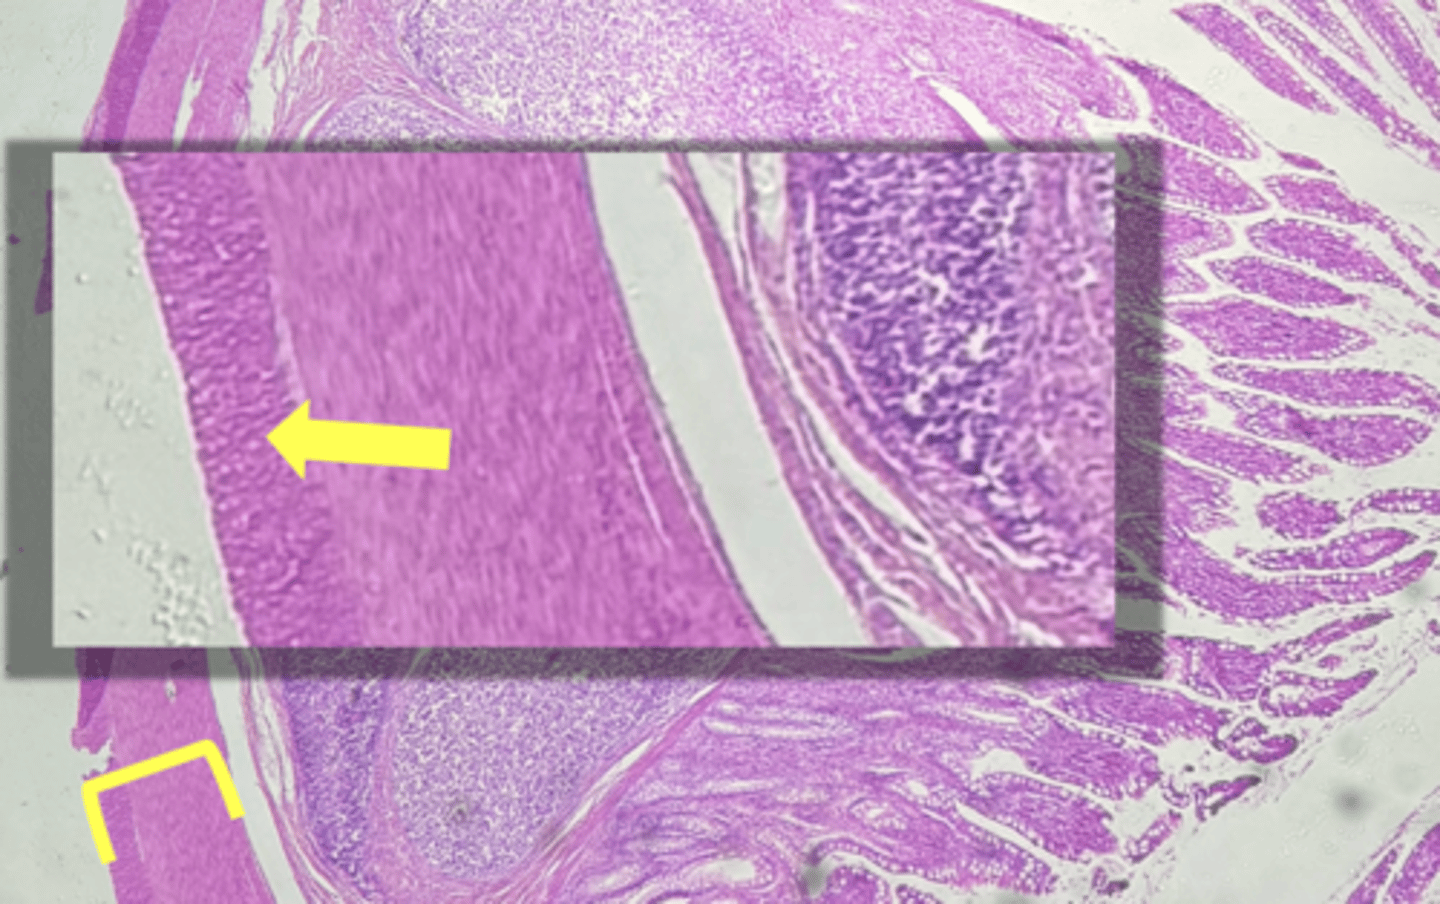

Esophagus

name the tissue

muscularis externa

(esophagus)

stratified squamous epithilium (KEY CHARACTERISTIC)

circular layer

longitudinal layer